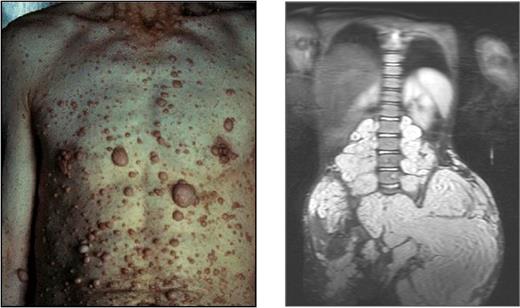

Mutations of NF1 predispose patients to variable neuronal, hematopoietic, and skeletal disorders, including myeloid leukemia, kyphoscoliosis, long bone pseudoarthrosis, and cutaneous, subcutaneous, and diffuse plexiform neurofibromas.6,17 Neurofibromas are pathognomonic for the disease. Cutaneous neurofibromas arise from small peripheral nerves during adolescence or adulthood and are observed in greater than 95% of patients with NF1 (Figure 1 left).18 Plexiform neurofibromas, by contrast, appear in approximately 15% to 40% of patients with NF1 and arise during early development from cranial nerves and proximal large peripheral nerve sheaths (Figure 1 right). These interdigitating tumors are composed of Schwann cells, fibroblasts, degranulating mast cells, and vascular cells.6,19 Although cutaneous neurofibromas have limited growth and a very low propensity for transformation, plexiform neurofibromas can constitute an early and lifelong source of disfigurement, disability, mortality, and potential transformation to a metastatic malignant peripheral nerve sheath tumor.

Examples of cutaneous and plexiform neurofibromas. Cutaneous neurofibromas growing on the chest and abdomen and an magnetic resonance image of a large plexiform neurofibroma compressing the spinal column. Photographs courtesy of the Children's Tumor Foundation; www.ctf.org.